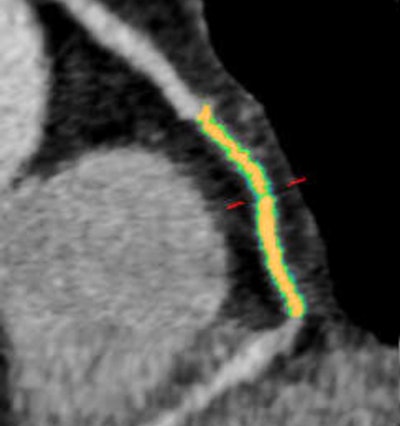

Woman age 61 years with a history of arterial hypertension, hyperlipidemia, and an abnormal stress test. Initially, CT angiography revealed patent coronary arteries and no significant stenosis, but after the patient had a myocardial infarction, a retrospective plaque analysis showed a 75% reduction in lumen volume in the mid right coronary artery; the culprit plaque had a lipid component of approximately 60% and a fibrotic component of about 40%. The mid right coronary artery was the most common location for culprit plaques in the patient cohort. Image courtesy of Dr. Stefanie Mangold and Stephen Fuller.Session moderator Dr. Filippo Cademartiri from the Montreal Heart Institute asked if it was difficult to obtain accurate plaque assessments given that the regions of interest selected for analysis might contain vessel wall or small areas of several kinds of plaque that could confound the analysis.